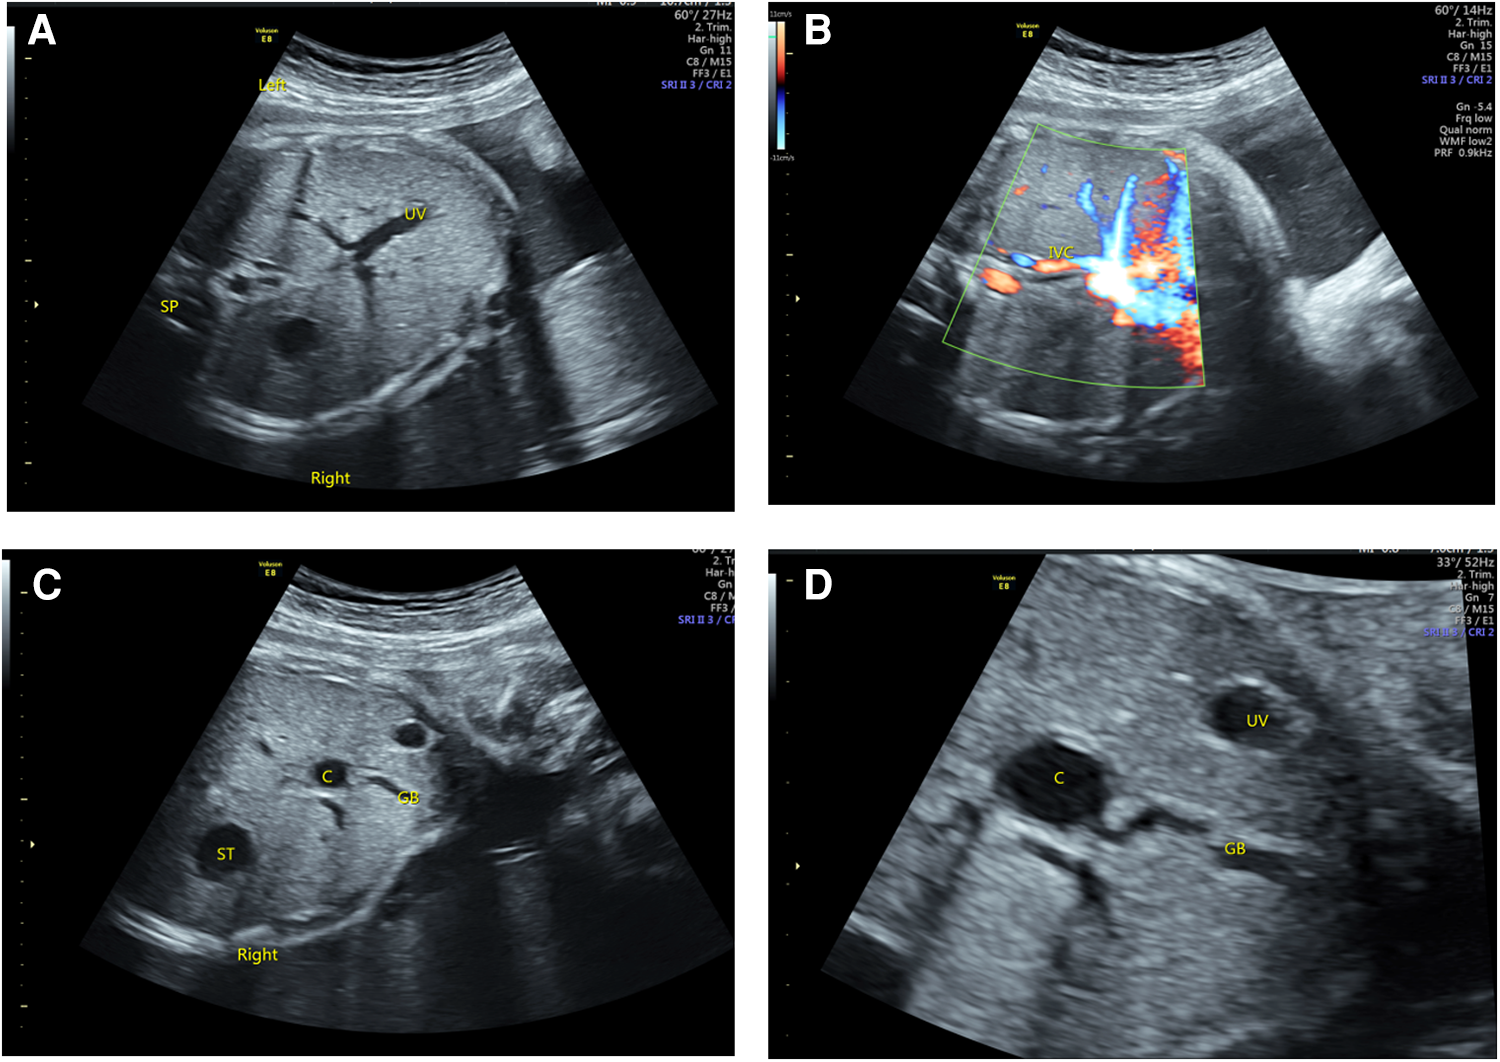

Figure 3

Ultrasonography of BASM in LAI fetuses. (A) The right-sided stomach and the portal vein branch show a “T” sign. (B) The IVC was small and flowed back to the right atrium after collecting hepatic vein blood. (C,D) A cystic structure was observed in the liver hilum, which was related to the gallbladder.